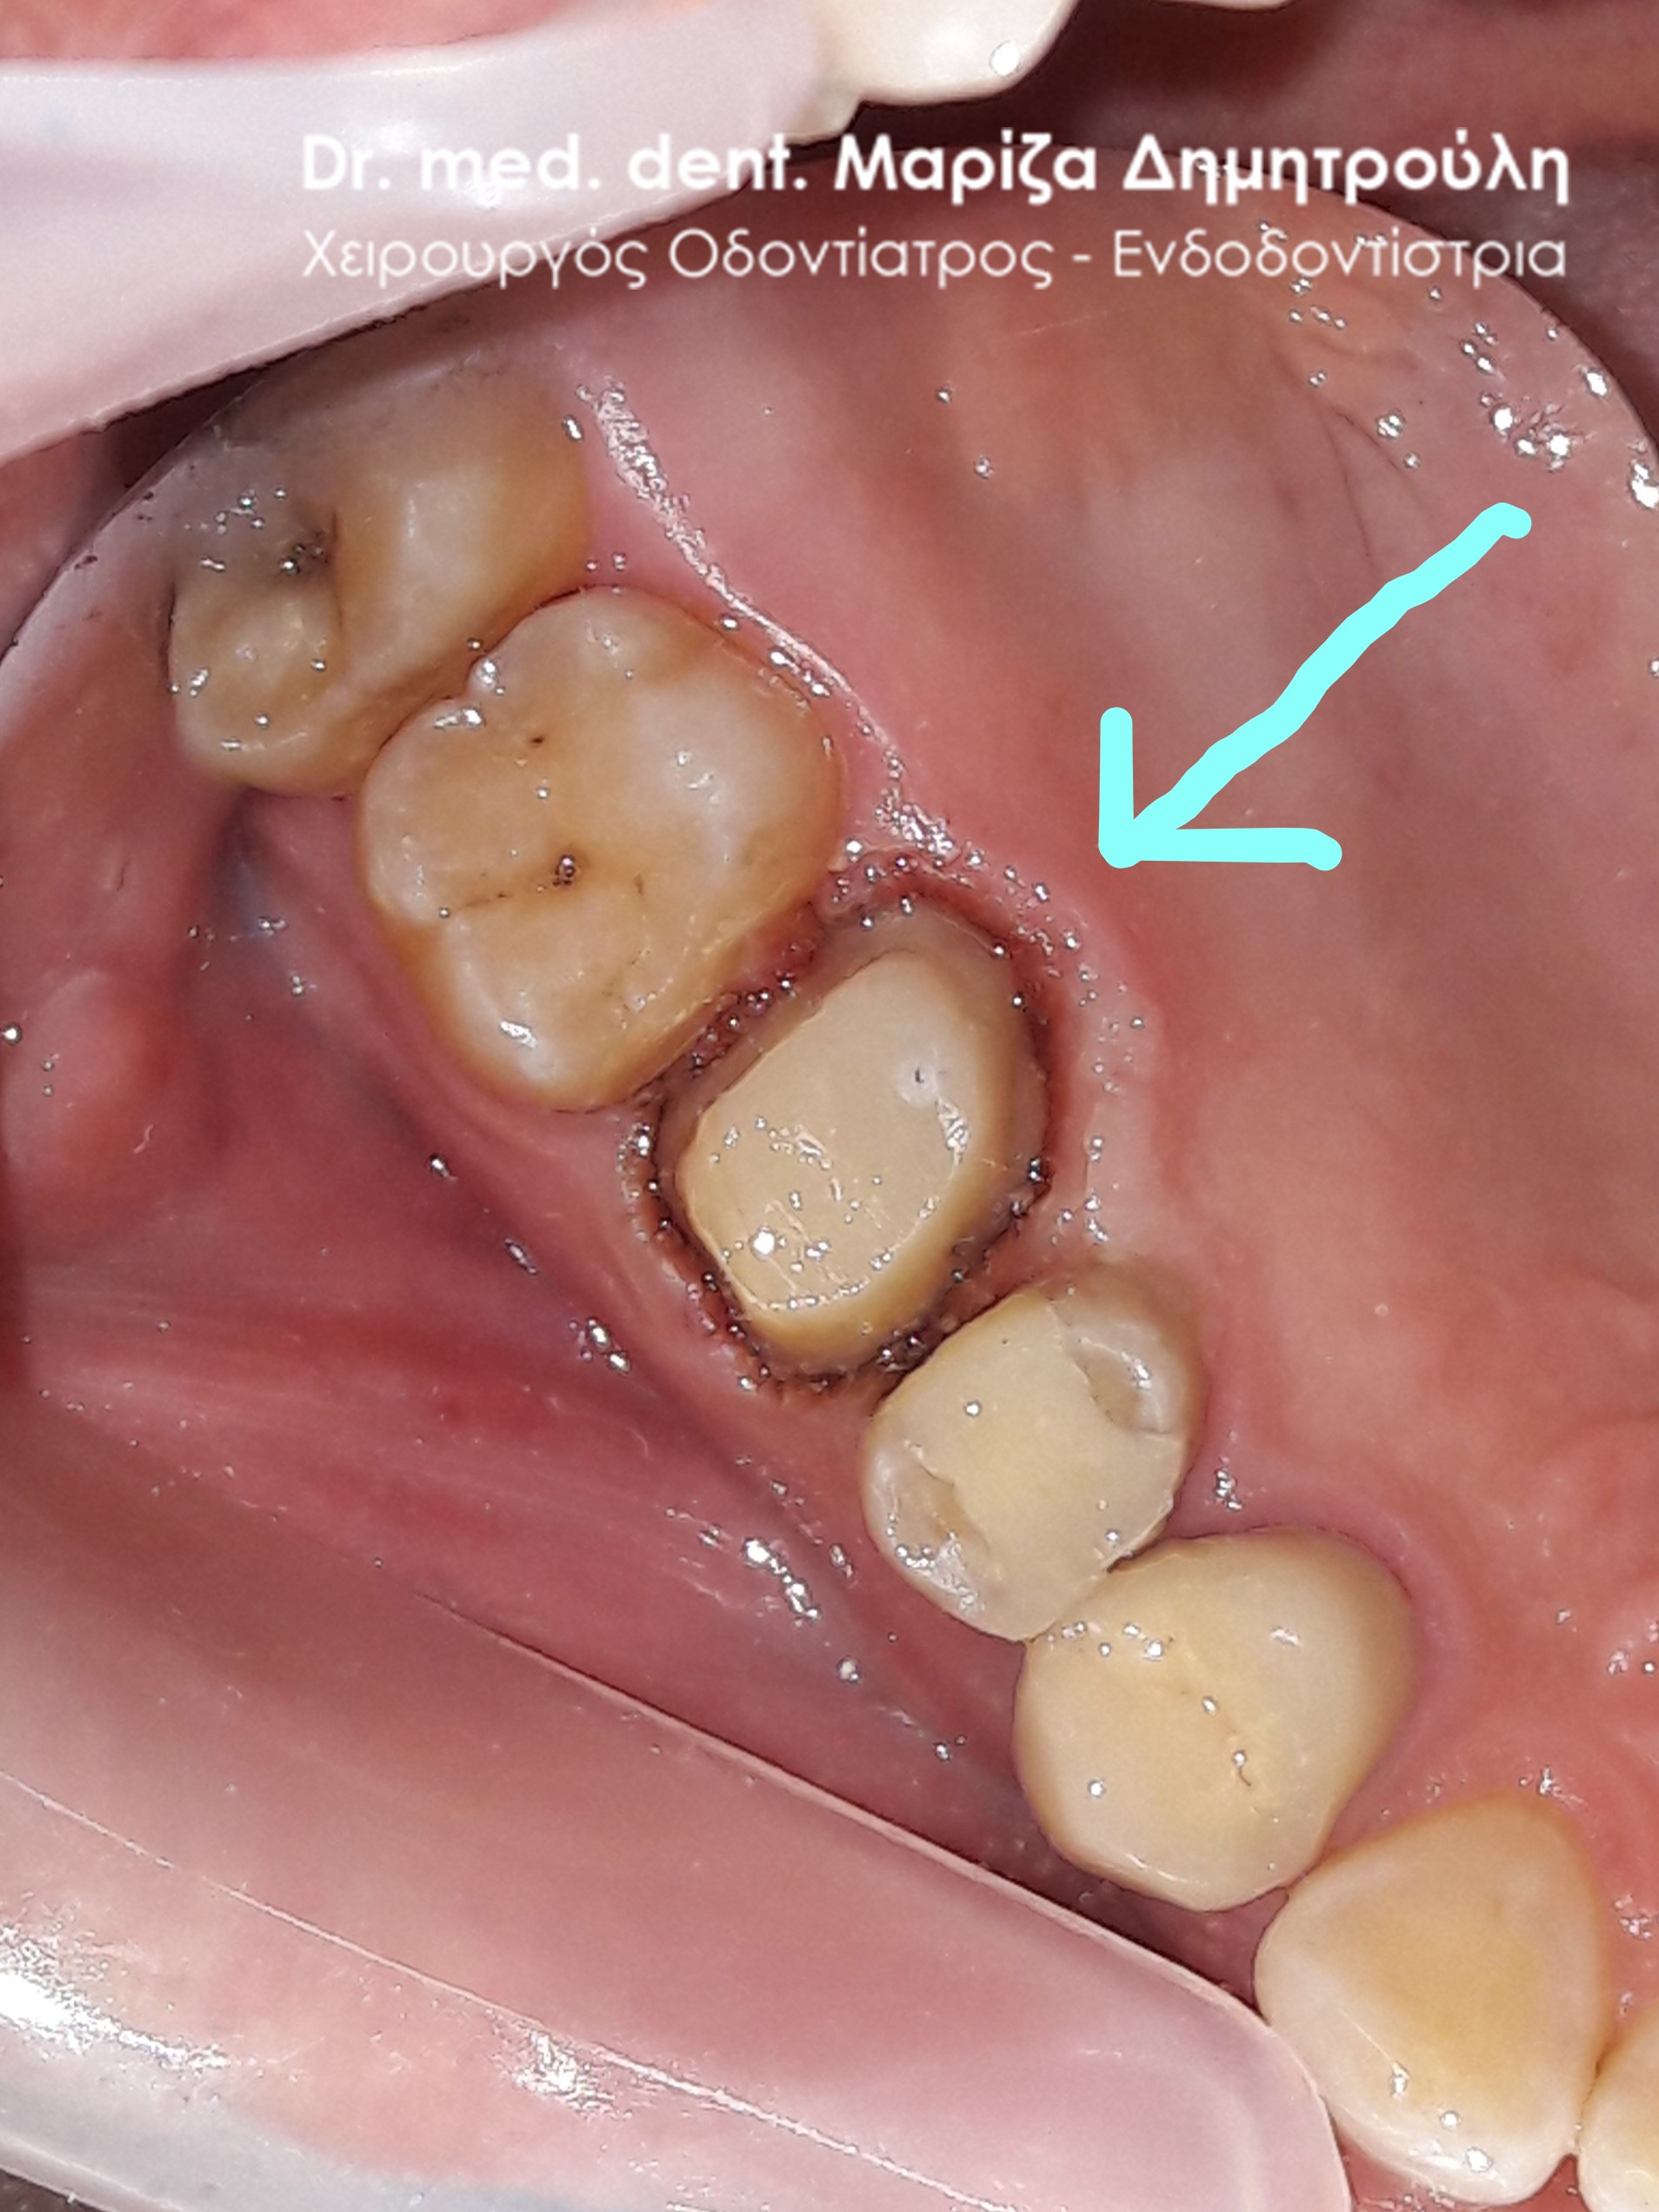

Περιστατικό – Ολοκεραμική στεφάνη / θήκη ζιρκονίου στον άνω αριστερό γομφίο

Επιθυμία του ασθενή ήταν η αποκατάσταση του άνω αριστερού γομφίου, ο οποίος είχε ένα παλιό μεγάλο επανατερηδονισμένο λευκό σφράγισμα. Μετά την αφαίρεση της παλιάς έμφραξης, ακολούθησε η ανασύσταση του δοντιού, ο εκτροχισμός του και η λήψη αποτυπώματος. Ο οδοντοτεχνίτης κατασκεύασε ολοκεραμική θήκη, η οποία κολλήθηκε στο δόντι με ρητινώδη κονία. Το δόντι είναι πλήρως προστατευμένο και ο ασθενής το αισθάνεται πολύ σταθερό.

Αρχική κλινική εικόνα του δοντιού με το παλιό σφράγισμα

Ανασύσταση και εκτροχισμός του δοοντιού